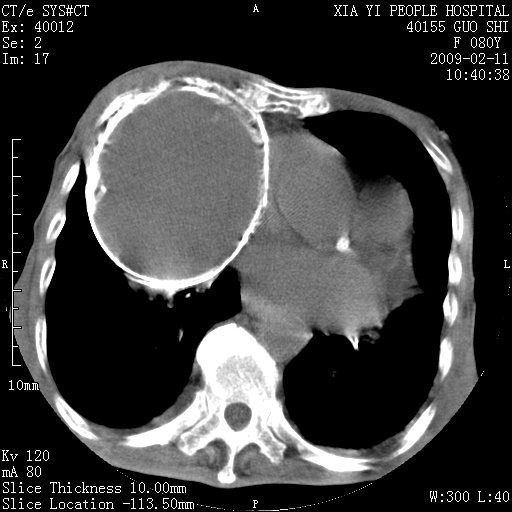

以下是引用随光逐影在2009-2-16 16:34:00的发言:[br]1)考虑右前纵隔皮样囊肿。2)双侧少量胸腔积液。

以下是引用zjzjr在2009-2-16 17:30:00的发言:[br]支持囊性畸胎瘤 双侧少量胸腔积液。